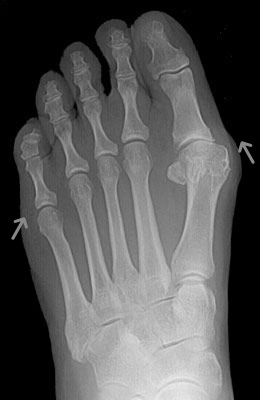

Before

Lapidus Forever Bunionectomy™ Before image

After

Lapidus Forever Bunionectomy™ after image

Lapidus Forever Bunionectomy™

Whitney, a 47-year-old businesswoman who could not fit into her dress shoes because of her bunion and terrible calluses caused by it. We performed a Lapidus Forever Bunionectomy™ on her big toes and she was able to bear weight on her foot 2 weeks after surgery and was back in her heels at 8 weeks post-surgery with no pain and now an amazing looking foot. After image was taken 12 weeks post-op.